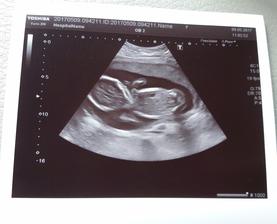

Náš zázrak 2017

Zázrak se snad stane skutečností...